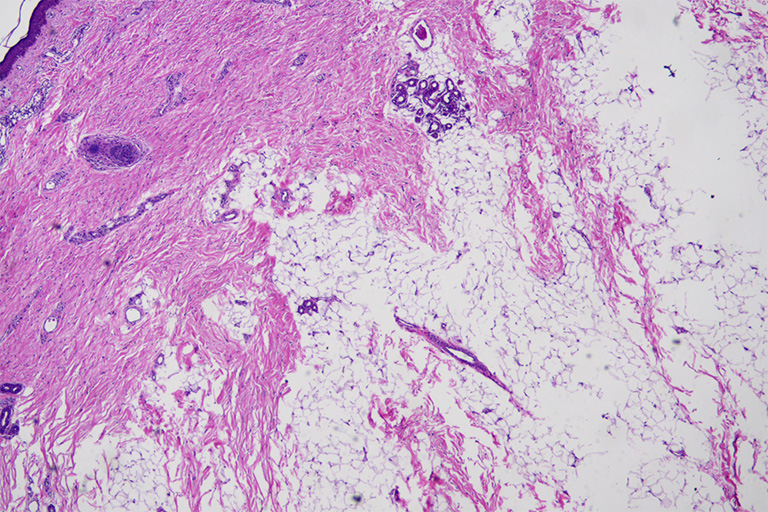

2例患儿均行全麻下眼睑肿物切除及眼睑成形术,术中探查见2例眼睑肿物均与颞侧球结膜粘连并延伸至外眦部眼球表面,基底部蒂较宽,眼球表面结膜肿物为淡黄色,质软,包膜薄,表面有毛发,与球结膜及筋膜相粘连(图3),外眦部部分睑缘缺损(图4)。沿肿物与皮肤延续的基底部切除皮肤肿物,同时切除结膜表面肿物,对睑缘凹陷及缺损部位进行对位修补及眼睑成形(图1、图2)。病理检查示:皮赘伴结膜皮样脂肪瘤,结节样肿物表面被覆鳞状上皮,皮下见皮肤附属器及分化成熟的纤维脂肪血管组织(图5),病例2局灶见钙化(图6)。

20221226171859_9769.png

图5 病例1病理示肿物表面被覆鳞状上皮,皮下见皮肤附属器及分化成熟的纤维脂肪血管组织(HE,×40)

Figure5 Histopathological description of the mass photomicrograph of case 1 showing skin appendages and mature fibroadipose vascular tissues were surrounded by squamous epithelium (HE, ×40)